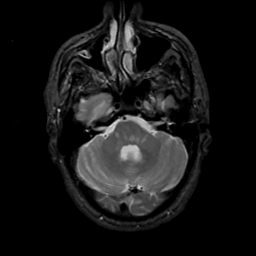

MR Study #6, March 17, 1991 -- Slice #12